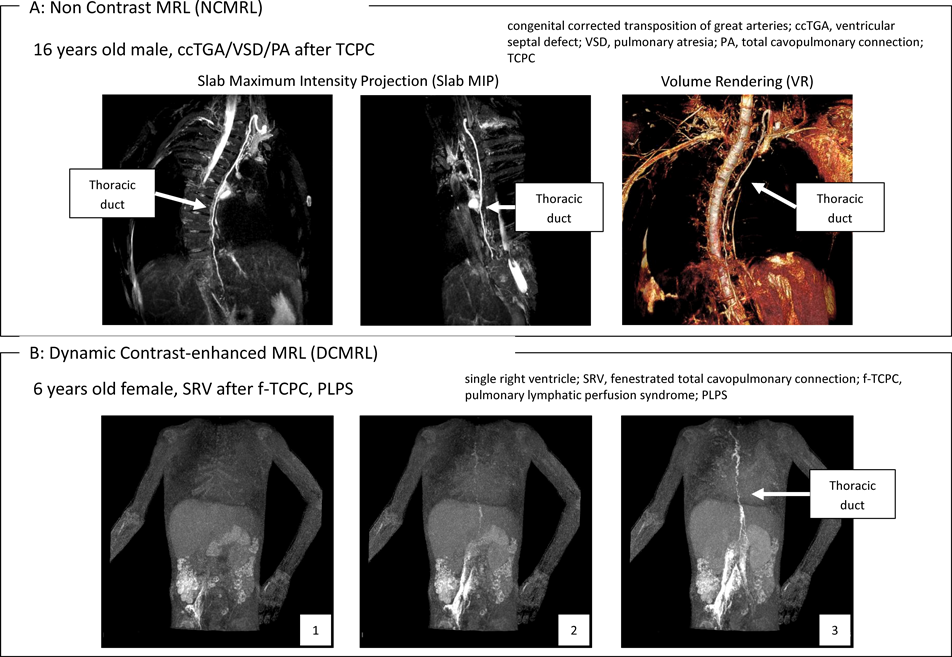

NCMRL

NCMRLは,脂肪抑制をかけながらT2強調3次元高速スピンエコー(T2 weighed 3D-fast spin echo: T2W 3D-FSE)法を使用して得られたheavily T2強調画像によって,リンパ管を高信号に描出する撮影法である(Fig. 7A37)

Fig. 7 MRL (Magnetic Resonance Lymphangiography)

heavily T2強調画像はMR水強調画像(MR hydrography)とも呼ばれており,長いT2値を持つ生体内の水を高信号に描出する38).すなわち,NCMRLは「リンパ管内のリンパ液」を描出することで,間接的にリンパ管を描出する撮影法である.ただし,胸水や腹水など体腔内に貯留した液体,浮腫など組織間隙に貯留した水分,さらには静脈内にある血液などといったリンパ以外の水も描出されてしまうため,画像の解釈には注意が必要である.

特徴と応用

NCMRLの特徴は,非侵襲的にリンパ管の形態評価ができることである.このような特徴を活かして,胸部外科手術における胸管損傷を予防するためのスクリーニング(胸管の形態把握)39, 40),胸部外科手術後の胸管損傷部位の同定41),Fontan術後の中心静脈圧上昇に伴う胸管の形態変化の観察42)などの評価に利用されている.

DCMRL

DCMRLは,リンパ管内にGd造影剤を注入し,脂肪抑制をかけながらT1強調3次元グラジエントエコー(T1 weighed 3D-gradient echo: T1W 3D-GRE)法で複数回撮影することで,リンパ管を高信号かつ動的に描出する撮影法である(Fig. 7B36)

T1強調画像であるため,血液・胸水・腹水・浮腫など生体内に存在する水の影響を受けない画像が得られる.また,Gd造影剤を使用するため,信号雑音比とコントラスト雑音比が高い画像が得られる.